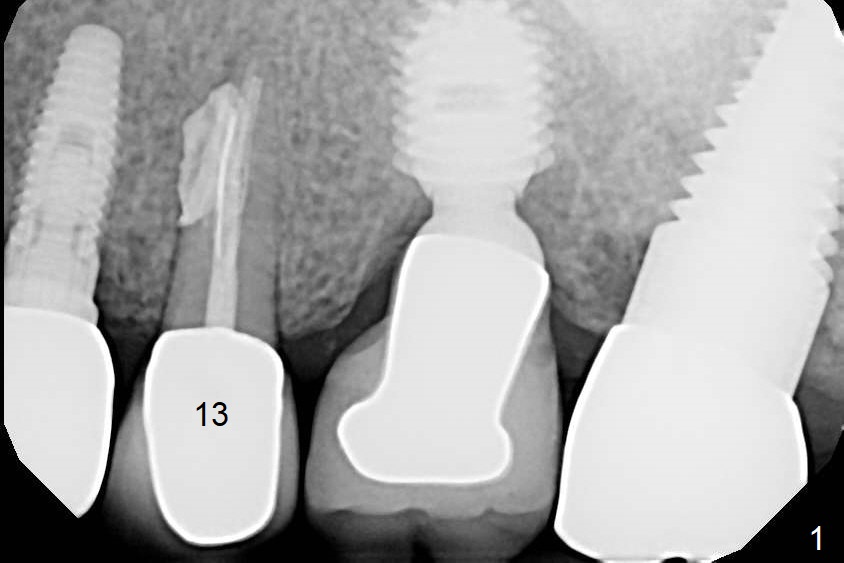

Failure

A 75-year-old man has bite pain at #13 after RCT (root resorption, Fig.1). The tooth appears to be non-salvageable (Fig.2). There seems to be sufficient bone for the longest tissue-level implant (Fig.3,4). Take preop PA and intraop one as soon as a 2 mm drill is used for trajectory confirmation.